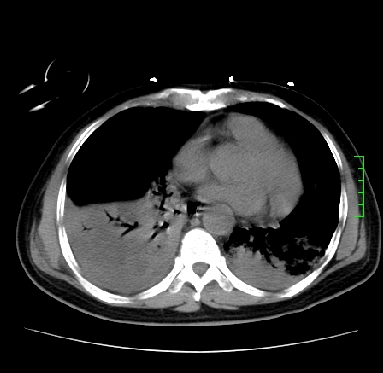

icu病人,几天都没明确诊断。m,76y,咳嗽、咳痰1周,伴气促,右胸痛入院,pe:t38.3c p135 r25 bp135/85。双肺可闻及大量湿罗音,心、腹未见明显异常。诊断:1心衰?2肺部感染?3冠心病?

双肺感染性病变,下叶膨胀不全,胸水,左室大。

1)两肺感染性病变(右肺下叶肺脓肿可能)。2)双侧胸腔积液,以右侧为甚。

ards,肺感染性病变,右下叶实变,双侧胸腔积液,右侧为著,叶间胸膜积液,右上肺陈旧性tb纤维灶,左室大。

考虑双肺感染、右肺下叶肺脓肿伴双侧胸腔积液,肺水肿。

考虑:双肺感染、右肺下叶肺脓肿,双侧胸腔积液,肺水肿.请结合临床.